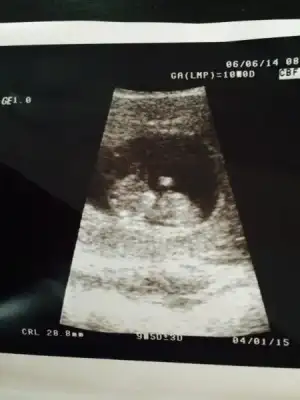

:34: bizim seninle aramızda 1 gün var. iki gün önceki ultrason görüntüsünü koydum. hala bişey diyen olmadı. ama benimkinde de çıkıntı net değil. bende tam anlayamadım. kız mı dedim kendi kendime. ama 1 oğlum var bu da kız olsun isterim yani, o yüzden mi kıza yoruyorum bilmiyorum. ama erkek nubu popoya paralel değil dik se eğer kız olma ihtimali daha yüksek bence. paralel net anlaşılmayabilir ama erkek anlaşılır bence, bu nub yöntemi aksi çıkan varmı bilmiyorumki

bak bu 2 gün önceki görüntü

pattosa bu usg sanırım 10 haftalık. . çok küçük çünkü henüz belli oaz bu haftada 11 hatta 12 hafta sonrası daha uygun..